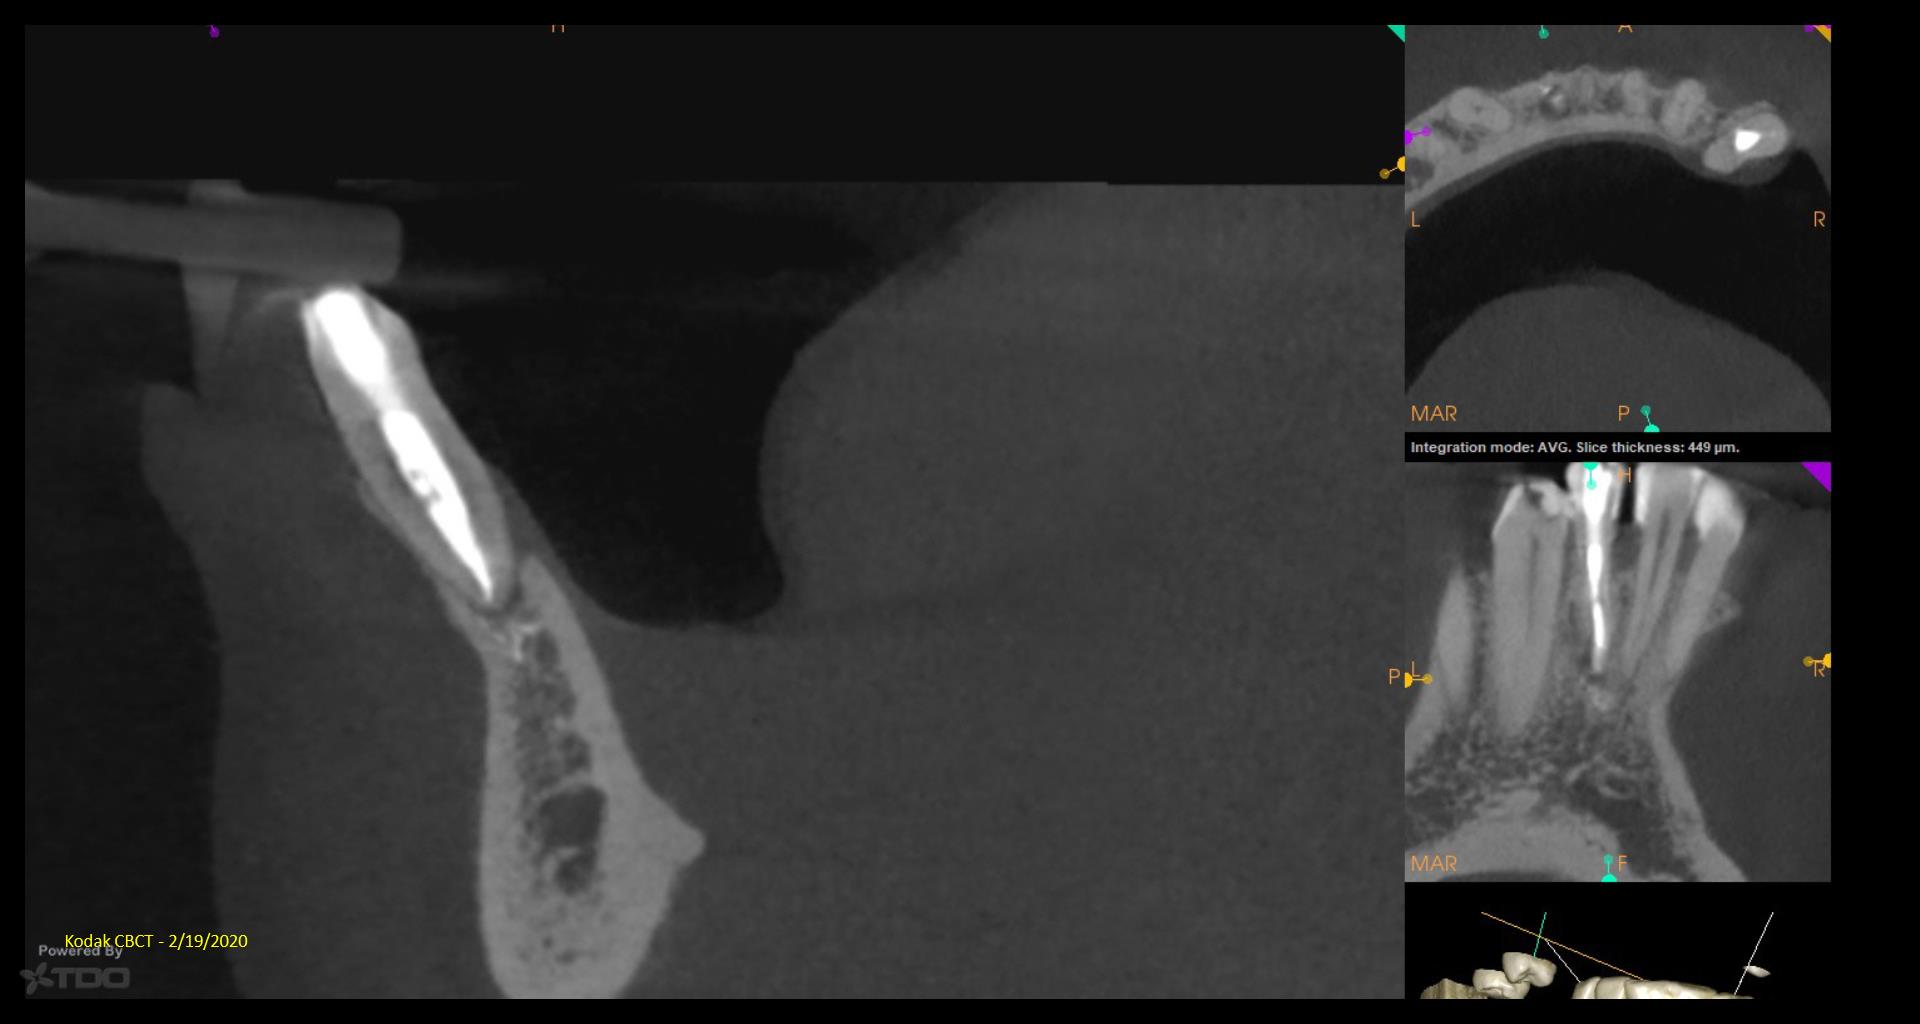

It’s a little embarrassing…but I have been treating a tooth of Joy’s for 5 years….Multiple CaOH visits over those 5 years. Coulod never get the area to resolve. Finally tried a GW on it…..1 yr recall today. gbc